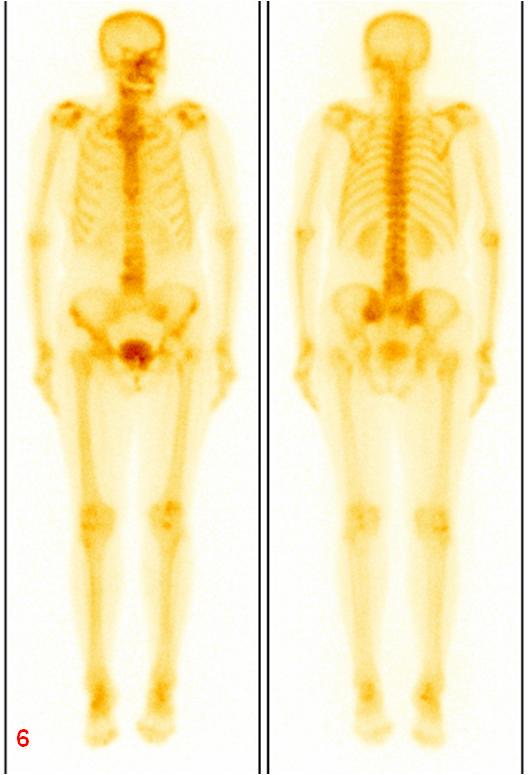

ECT全身骨顯像診斷為機(jī)能不全骨折,建議患者隨診復(fù)查。患者于1年后復(fù)查平掃CT及ECT全身骨顯像,綜合兩次影像學(xué)資料,考慮骨折修復(fù)愈合。

圖6復(fù)查ECT雙側(cè)骶髂關(guān)節(jié)、骶骨及左側(cè)恥骨代謝較前明顯減低。